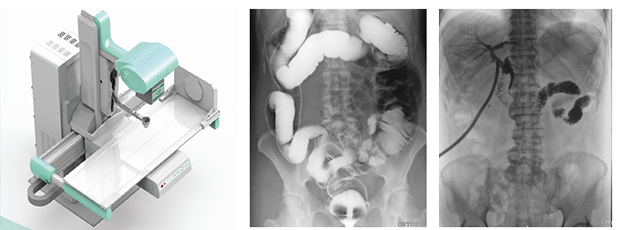

多功能動態dr由動態平板探測器、高壓發生器、球管、運動機架、計算機與圖像處理與傳輸系統組成,與傳統數字化X線攝影技術相比,動態多功能dr攝影能在一個時間單位內低劑量高速獲得多幀X線影像,通過圖像算法處理系統后,極速輸出一段連續動態影像(運動),實現所見即所得。

多功能動態dr可以理解為一種不同角度觀察器官運動的X光視頻。常規的靜態dr更多的顯示的是器官的投影像,單一角度單一時間點很難發現細微病灶。而多功能動態dr可以從不同的角度、時間來觀察器官的運動,診斷準確率會大大提升。

多功能動態dr是集合拍片,透視,造影三種功能為一體的設備。可以對特殊病灶部位進行高速實時點片,捕獲高清病灶圖,降低了漏診誤診率。特別是對不能配合的患者,也能進行快速高效的檢查,大大減輕了患者的痛苦。